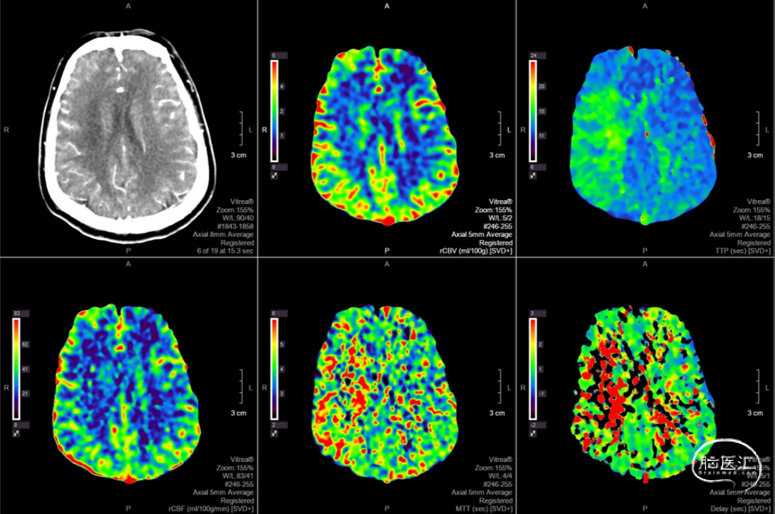

头颅CTP:右侧大脑中动脉区域明显低灌。

2. 头MRI示右侧半卵圆区新发脑梗死,右侧大脑中动脉M1段闭塞;代偿不佳,CTP示右侧大脑半球低灌注;高分辨率核磁共振:右侧大脑中动脉前壁强化斑块。

4. 术前CT灌注或DSA证实责任病变区域侧枝循环代偿不良。